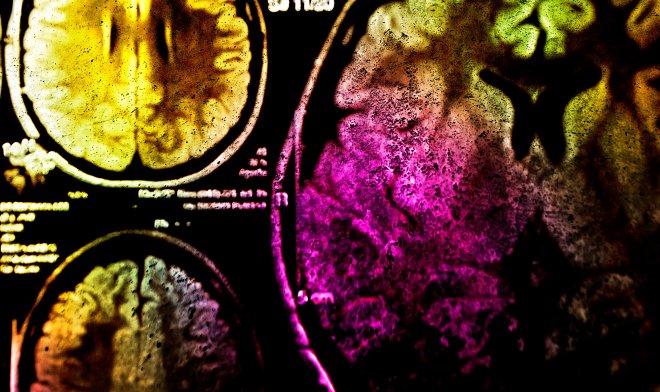

Для того чтобы не пострадали остальные живые ткани, синтетическую молекулу привязали к белку EGFR, основному элементу глиобластомы рака мозга. При проведении опытов на грызунах раковые клетки полностью погибали уже через час после воздействия инфракрасного излучения. Кроме того, такое вмешательство активировало иммунную систему, которая помогала справиться с остатками раковых клеток, поэтому технология и получила название «фотоиммунотерапия».